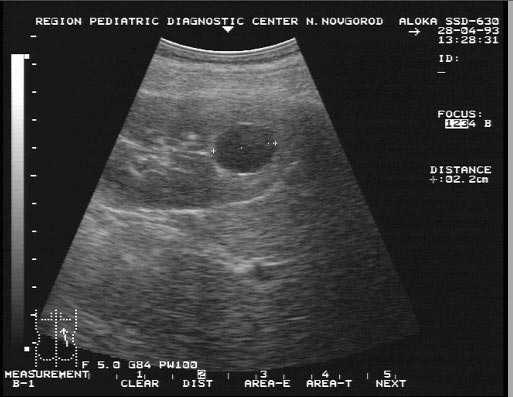

Операция по удалению кисты почки — Болезни почек человека, Кисты на почках (единичные и множественные)